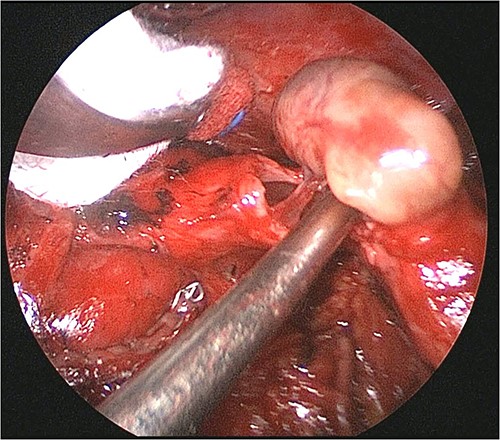

Video-assisted thoracoscopic surgery was used to perform a resection of the left lower lobe. The surgical procedure was carried out through a 4-cm surgical incision at the mid-axillary line of the fifth intercostal space, a 3-cm surgical incision at the mid-axillary line of the seventh intercostal space, and a 5-mm trocar incision at the midline and posterior axillary line of the sixth intercostal space. A 5-mm thoracoscope with a 30-degree view was used to perform the procedure. The left lower lobe bronchus was gradually resected after being incised. The tumor, which measured 1.8 × 0.8 cm, had grown a thin stalk attached to the left lower lobe bronchus. No invasion of the tumor into the surrounding tissue was observed (Fig. 3). The lower lobe bronchial stump was repaired with interrupted suture absorbable monofilament sutures. Pericardial fat was wrapped around the suture area. The postoperative course was uneventful, and the patient was discharged 9 days post-operation.

Operative findings. The tumor, which measured 1.8 × 0.8 cm, had a thin stalk attached to the left lower lobe bronchus. No invasion of the tumor into the surrounding tissue was observed.